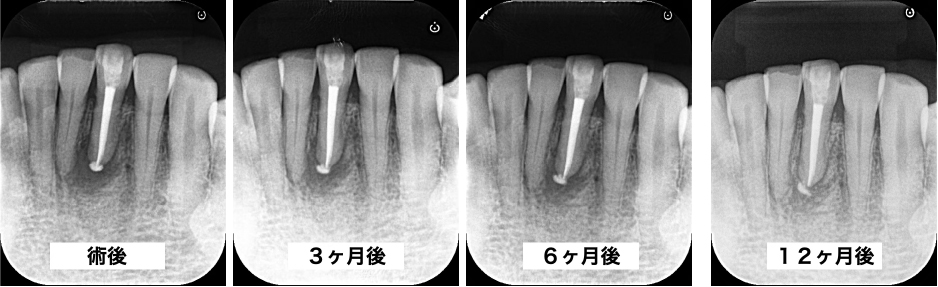

治療経過

術後、3、6、12ヶ月の経過観察を行いました。6ヶ月時点では根尖部の透過像は残っていましたが、12ヶ月時点で根尖部の骨吸収像は消失し、良好な経過をたどっています。

歯茎の腫れ(フォステル)も、術後6ヶ月時点で消失しました。

今後、さらに長期にわたり、骨組織はより成熟していくことが予想されます。